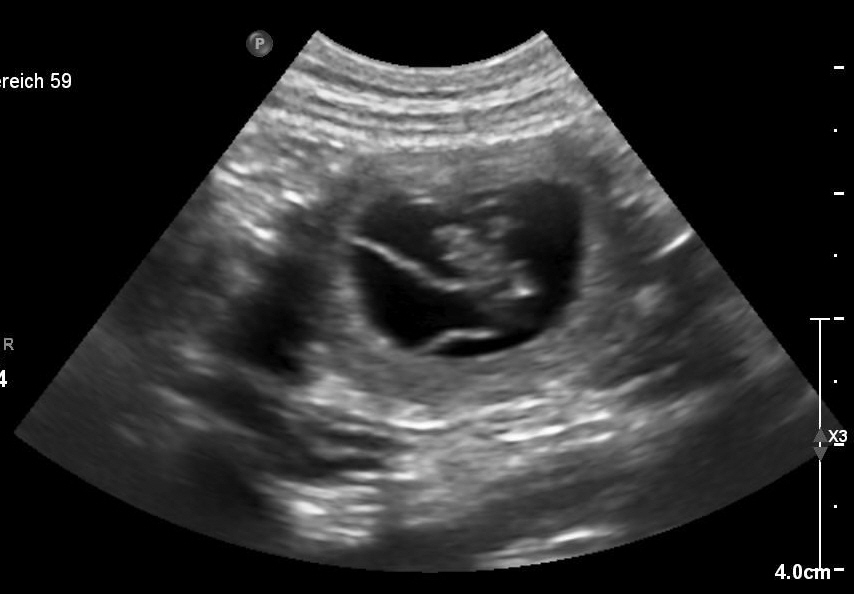

Heute am 04.12.2023 waren wir zum Ultraschall.

Ja, Volltreffer meinte der Tierarzt. Und so erwarten

wir Anfang Januar unseren B-Wurf.

Hurra!!! Lena ist trächtig!!! :)

Heute am 11.04.2023 war ich mit Lena zum Ultraschall und es wurden 5 Fruchtblasen festgestellt.

Der Wurf wird am 14.05.2023 erwartet!

28.Trächtigkeitstag.